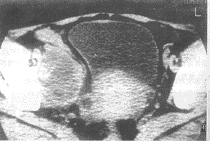

图3 透明细胞癌 CT平扫示左侧卵巢不规则形实性肿块,大小为7.0cm×6.0cm×5.5cm,伴有大量腹水 图4 腺癌 CT平扫示右侧卵巢不规则形囊性肿块,囊壁厚薄不均